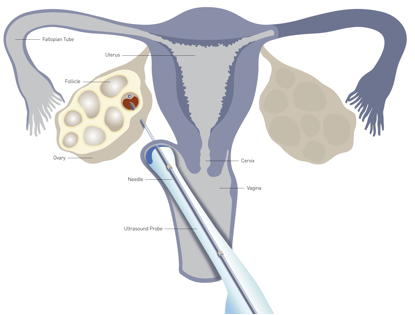

在门诊,患者经常会问:“医生,取卵手术到底痛还是不痛啊?为什么有的病友说没什么感觉、有些酸胀,有的病友说稍微有些痛、能忍受,还有病友却说非常痛、痛得死去活来……”...

试管婴儿过程是由一系列的步骤组成的,每一步都至关重要,取卵环节是医生完成的一个环节,很多患者对取卵很好奇,不知道试管婴儿所需要的卵子是如何从女性的体内取出来的。关...

正常生育年龄妇女每月可有一个卵泡发育成熟并排卵,而在辅助生殖治疗,特别是试管婴儿治疗中,为了在一个月中获得更多的卵子,医生常常会用到超促排卯治疗。超促排卵是指在严...

获得一定数量的优质胚胎是试管婴儿治疗成功的关键,因此获得高质量的卵子是目前临床控制性超促排卵(Controlled ovarian hyperstimulatio...